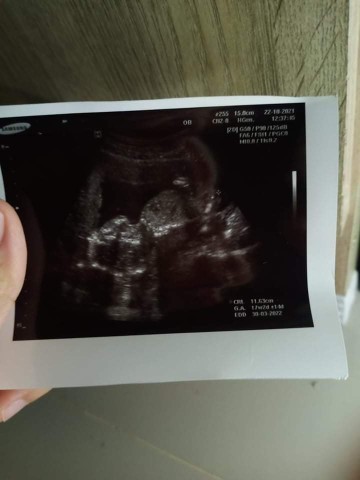

21สัปดาห์ ท้องแรกค่ะ😍